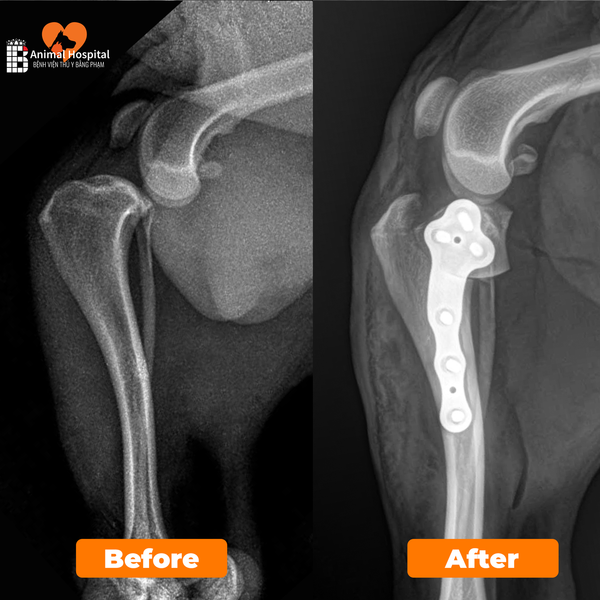

Đội ngũ bác sĩ Bệnh viện Thú y Bằng Phạm hội chẩn và thống nhất thực hiện phẫu thuật TPLO (Tibial Plateau Leveling Osteotomy) kết hợp chỉnh trật xương bánh chè.

• Kế hoạch trước mổ được thực hiện chính xác bằng phần mềm iBlueVet của BlueSAO, với các thông số phẫu thuật:

• TPA: 30°

• Lưỡi cắt: 15 mm

• Góc xoay: 6.5°

• Nẹp cố định: 6.5R TPLO Plate

Trong quá trình phẫu thuật, ghi nhận rãnh ròng rọc kém phát triểnsụn khớp không bao phủ hoàn toàn, và dây chằng chéo trước đã bị đứt hoàn toàn.

Phẫu thuật TPLO được tiến hành thành công, giúp tái định hướng lực tác động lên khớp gốiổn định lại mâm chày.